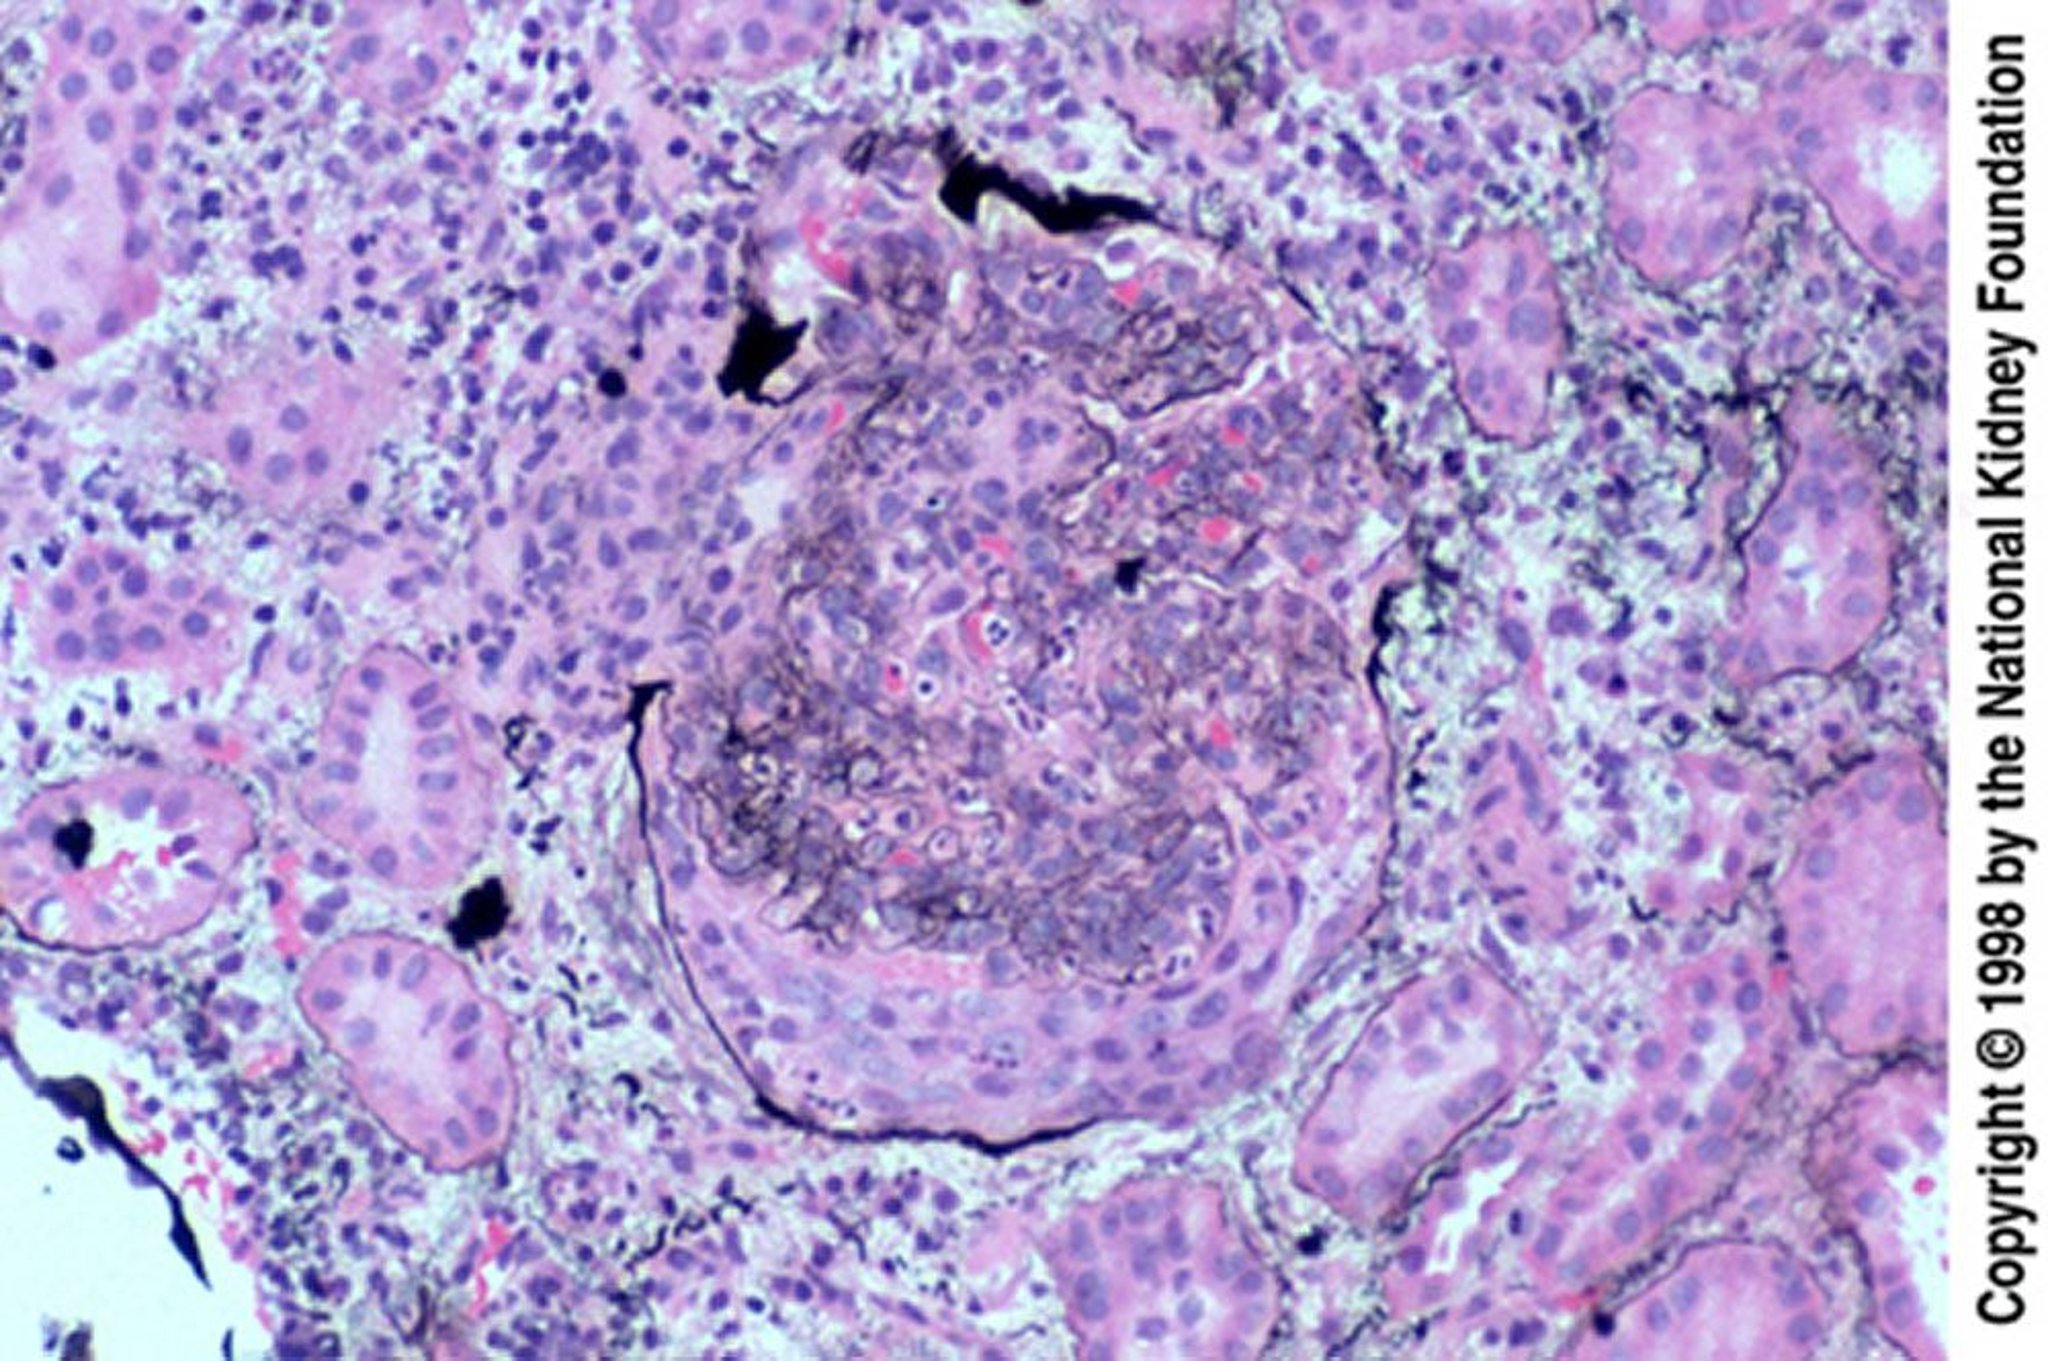

Постінфекційний гломерулонефрит (епітеліальні півмісяці)

Epithelial crescents are especially common when biopsy occurs late, after a failed response to treatment. The crescent has ruptured Bowman capsule (Jones silver stain, ×200).

Image provided by Agnes Fogo, MD, and the American Journal of Kidney Diseases' Atlas of Renal Pathology (see www.ajkd.org).